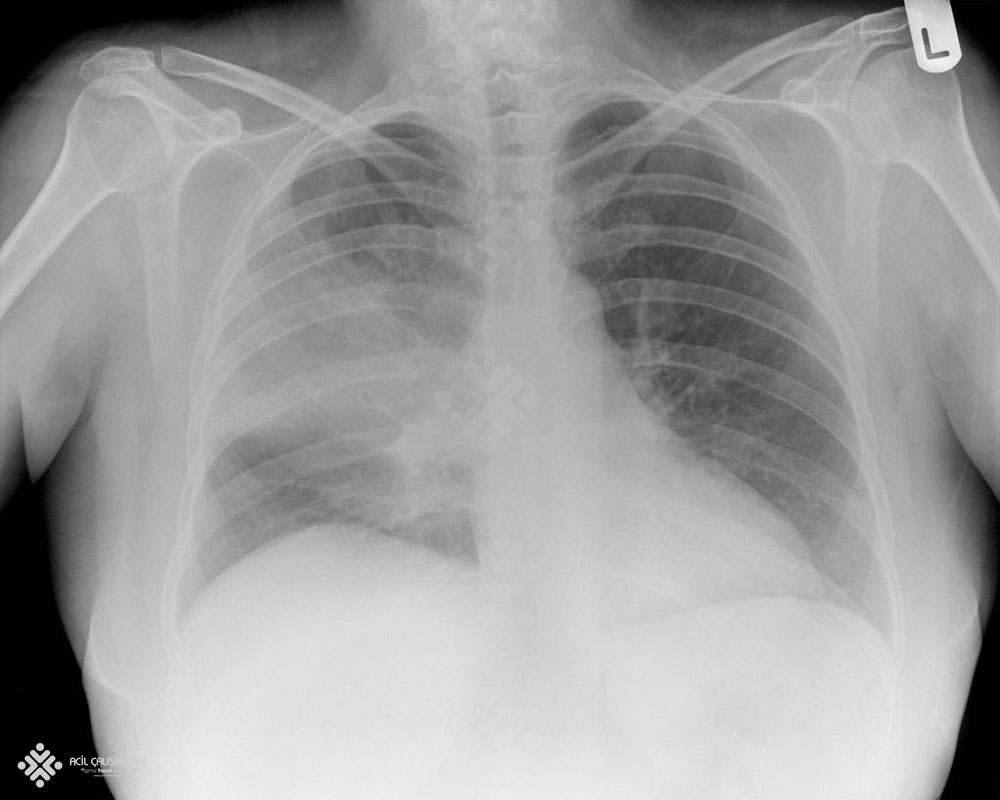

31 yaşında erkek hasta 4 gündür süren yüksek ateş, öksürük ve yeşil renkte balgam çıkarma şikayetleriyle acil servise başvuruyor. Anamnezinden diyabet hastalığın olduğu, şikayetlerinin her gecen gün arttığı , sınıf öğretmeni olduğu öğreniliyor. Hasta yeşil alan doktoru tarafından; GKS'u 15 Nabız: 96 atım/dk düzenli ; Ateşi 38,7 °C ; Solunum sayısı: 18/dk ; SpO2: 98 ; KŞ: 100 ve Kan Basıncı: 120/80 mm/Hg olarak değerlendiriliyor. Fizik muayenede; sol akciğer solunum sesleri azalmış ve orta zonda ral duyuluyor diğer sistemler doğal olarak değerlendiriliyor. Acil hekimi aşağıda görüldüğü gibi hastadan PA akciğer grafisi istiyor. Bu bilgilere göre bundan sonra hastaya uygulanacak en uygun yaklaşım ne olmalıdır?

Uygun semptom ve fizik bakı bulguları varlığında, akciğer grafisinde infiltrasyon görülmesi tanı için yeterlidir.Tedavi